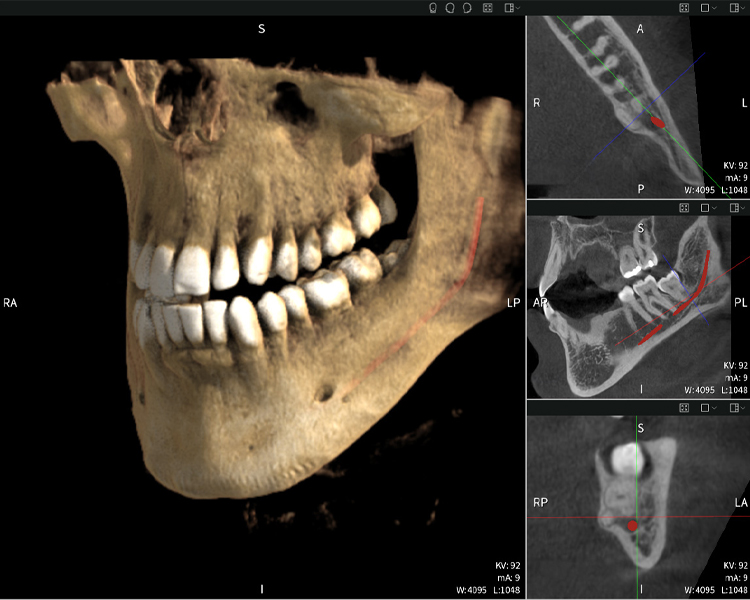

A continuación encontrarás un caso del Dr. med. dent. Oliver A. Centrella, en el cual las imágenes CBCT obtenidas con Seethrough Max proporcionaron información crucial sobre la anatomía compleja y la relación crítica entre las muelas del juicio y el nervio alveolar inferior. En este caso, existe una indicación para la extracción quirúrgica de las muelas del juicio.

Figura d: Resultados de imagen de Seethrough Max, sobre un fondo negro.

Figura d

Las figuras b–d muestran varias vistas de una reconstrucción 3D de la mandíbula, proporcionando una visión general completa de la anatomía mandibular, la posición de los nervios en relación con los dientes y permitiendo evaluar la simetría y alineación dentaria.

La figura d muestra el diente 48 previamente tratado, con la corona retirada y las raíces dejadas en proximidad al nervio, lo que ilustra el alto riesgo de daño nervioso.